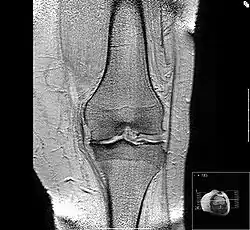

MRI of osteoarthritis in the knee, with characteristic narrowing of the joint space -